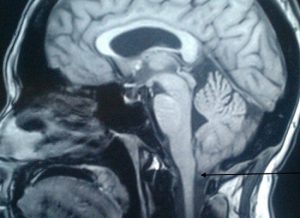

Наилучшим способом диагностирования патологии считают МРТ. Рентген и томография с помощью компьютера не показывают всей картины болезни.

Дистопия миндалин мозжечка — это специфическое опущение мозжечкового миндалевидного тела в крупное затылочное отверстие. Данную патологию могут именовать мальформацией Киари, происходит когда имеет место каудальная дислокация миндалевидного тела правой либо левой части головного мозга. Для болезни характерно пониженное стояние миндалевидного тела.

Эктопия миндалины мозжечка содержит в себе изменение в формировании мозжечка, включающее смещение, неправильную локализацию и пролабирование миндалины мозжечка. В научных кругах именуется как синдром Арнольда-Киари, а также дистопия миндалин мозжечка.

- Магнитно-резонансная томография. Определяется увеличенный объем желудочков мозга, IV желудочек смещен книзу. Мезэнцефалон удлинен и внедрен в мозжечок.